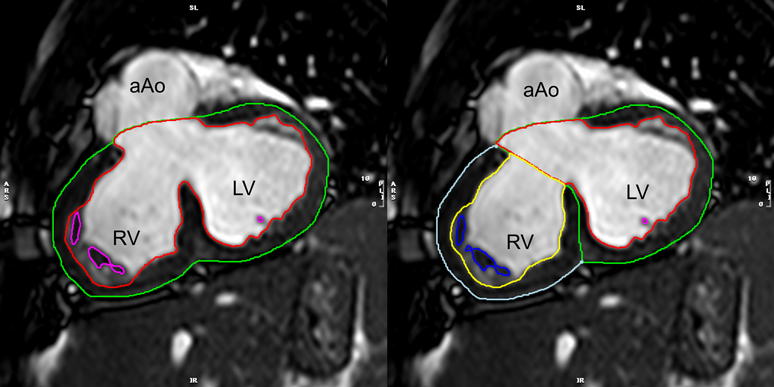

単心室症例には,解剖学的単心室症例(左右心室のいずれかが低形成・瘢痕的)と機能的単心室症例(左右心室いずれも容積はしっかりある)とがあるが,いずれの場合にも血行動態的には単心室として機能している.このため,駆出率などの計測をする際には,左心室・右心室をあわせて1つの心室としてトレースするのがよい(Fig. 1019).ただし,二心室修復可能かどうかの評価目的などで,左心室・右心室それぞれの拡張末期容積や駆出率が必要な場合は,術後の中隔線をイメージしながら仮想的に心室中隔を設定して左右心室を分けてトレースをすればよい(Fig. 10).

Fig. 10 Ventricular chamber quantification in a functional single ventricle. Left: Traced as a univentricular heart. Right: Traced as a biventricular heart

aAo, ascending aorta; LV, left ventricle; RV, right ventricle